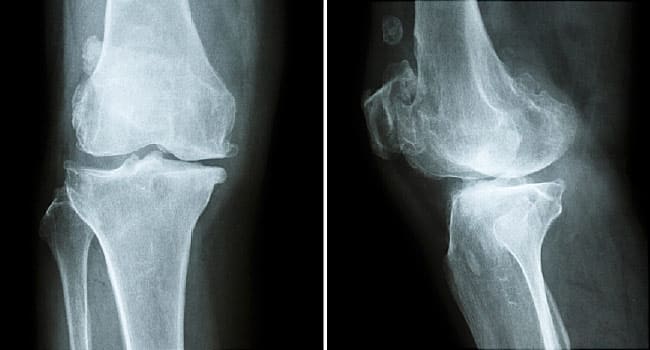

L’osteopenia determina una maggiore predisposizione alle fratture ossee, condizione causata da una riduzione dei livelli di densità minerale ossea. In pratica le ossa sono più fragili e quindi più soggette a fratture. Tale disturbo si presenta generalmente in età molto avanzata ed in tal caso è considerato fisiologico. Talvolta il problema si manifesta subito dopo la menopausa ed è collegato ad un calo naturale degli estrogeni e degli ormoni necessari per il normale metabolismo osseo. Si chiama osteopenia porotica, cioè derivante da alterazioni degli ormoni. Si parla invece di osteopenia malacica quando gli osteoblasti producono naturalmente la matrice, che però non riesce a nutrirsi di sali di calcio necessari per il rinforzo delle ossa. Altre forme sono l’osteopenia displastica, che si presenta in modo molto precoce, e l’osteopenia necrotica dovuta ad alterazioni microcircolatorie locali. Le persone che soffrono di osteopenia non presentano sintomi specifici, ma sono più soggette alle rotture ossee ed inoltre le fratture impiegano più tempo a guarire. Le cause principali sono l’invecchiamento ed i fattori ormonali, come un calo di testosterone negli uomini e di estrogeni nelle donne. Un’attività fisica scarsa o assente o una dieta squilibrata possono favorire la comparsa dell’osteopenia. Altri fattori che incidono sono l’abuso di fumo ed alcol, soprattutto nei soggetti predisposti, e determinate terapie farmacologiche che, se risultano forti e prolungate, possono indebolire le ossa.